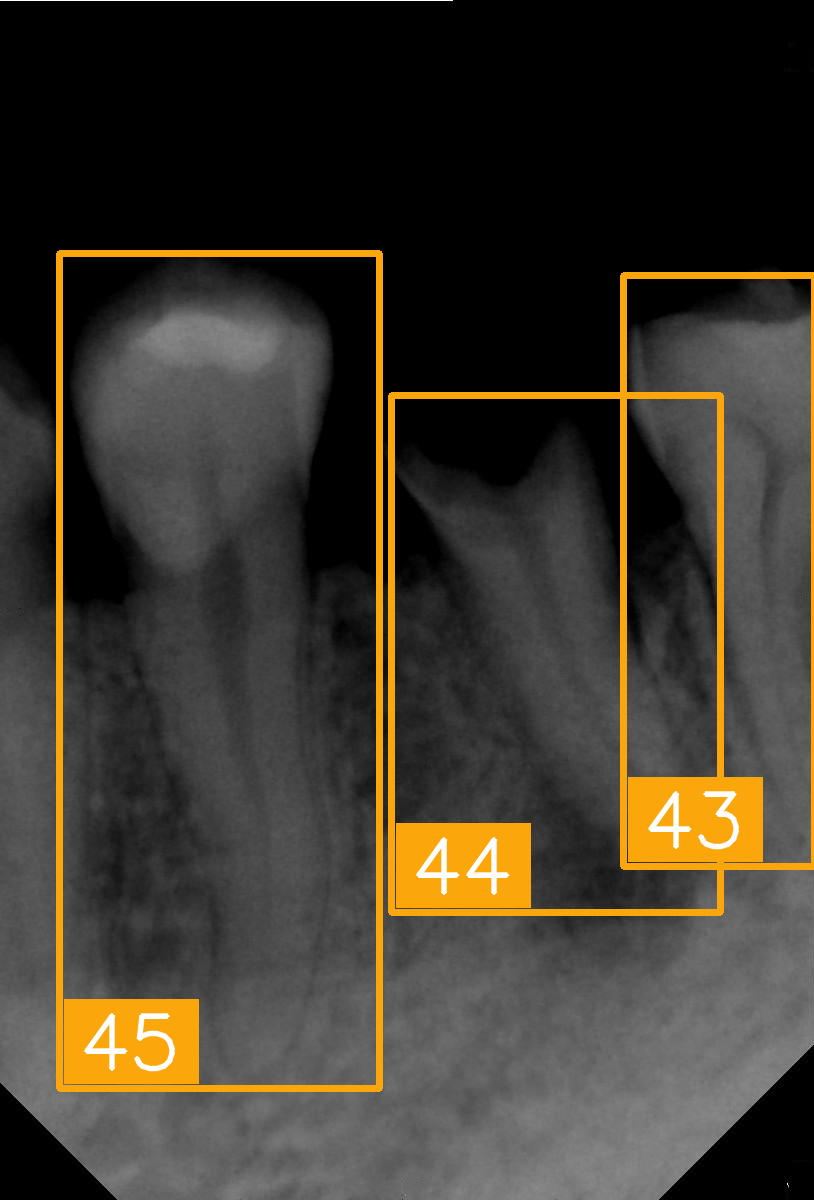

| Number | (e) | (f) | (g) | (h) |

| Condition | Fractured tooth; lower brightness | Overlapping | Implant | Implant |

| PA | ![]() | ![]() | ![]() | ![]() |

| FDI ground truth number | 45, 44, 43 | 32, 33, 34, 35 | 16, 15, 14, 13, 12 | 24, 25, 26 |

| Inference Time | 72.8 ms | 77.2 ms | 70.6 ms | 72.4 ms |